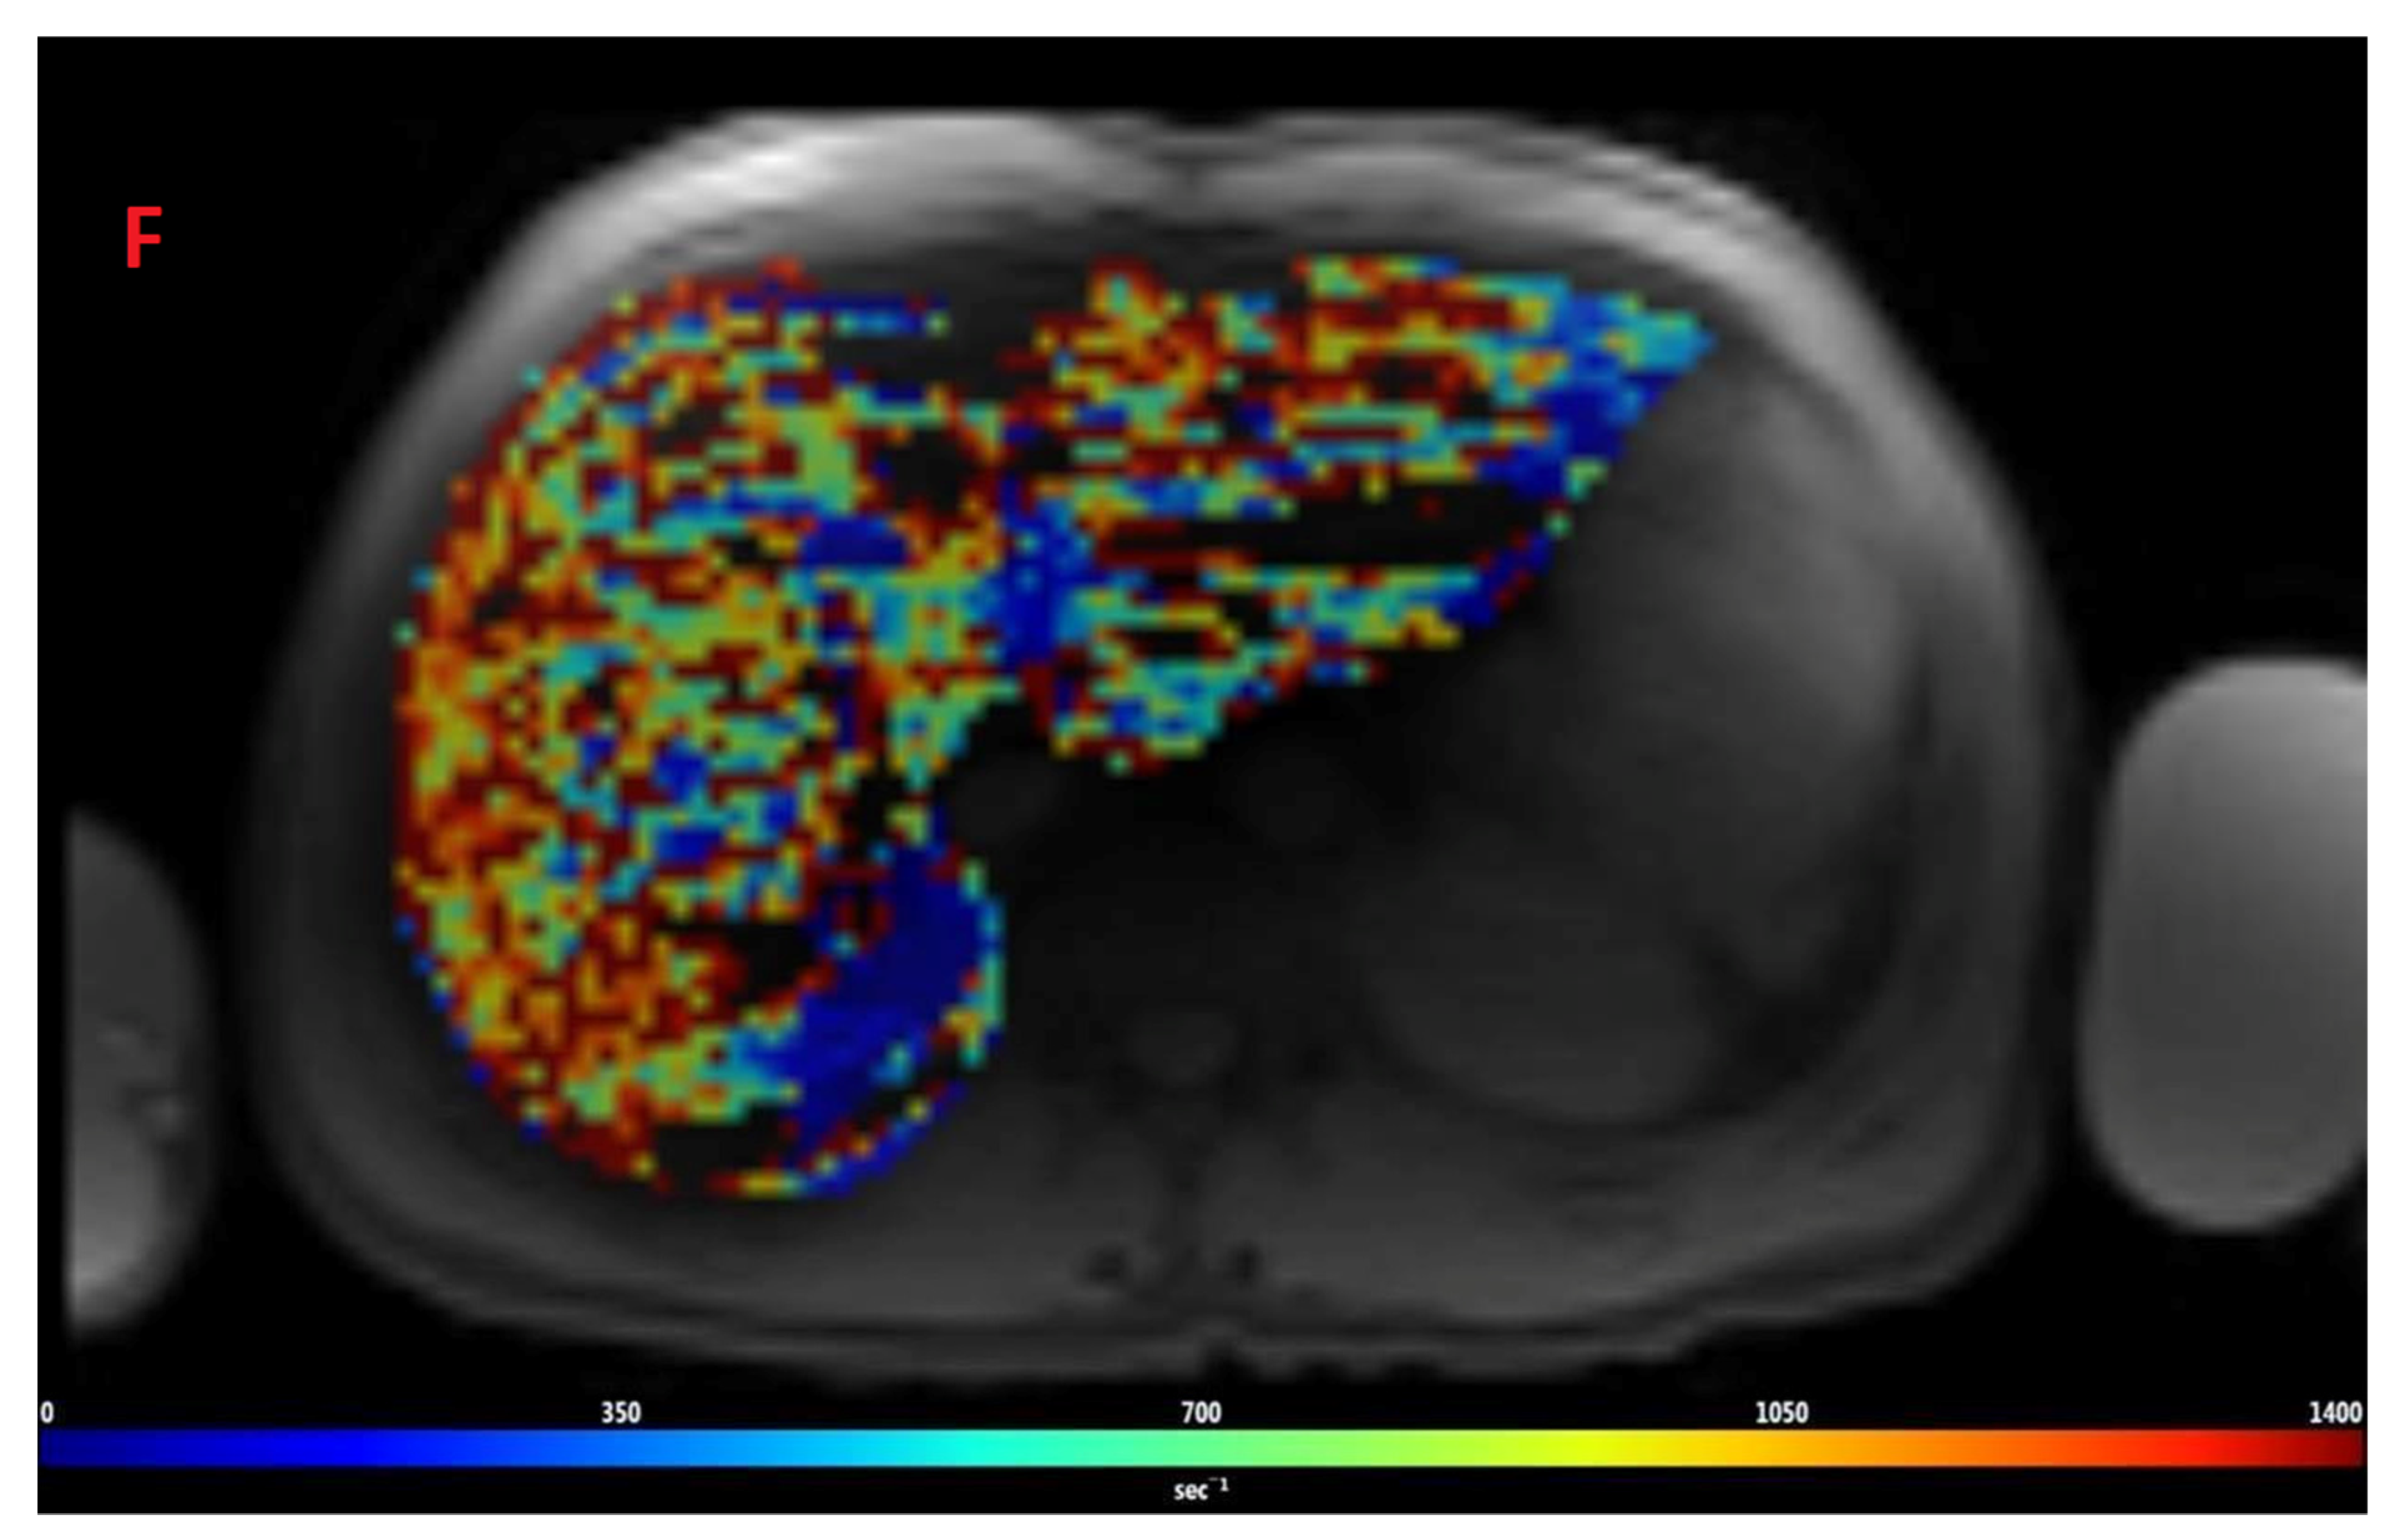

2.1.1. Spin-Echo Imaging (R2 Relaxometry)

2.1.2. GRE Imaging (R2* Relaxometry)

2.2. Post-Processing of Images